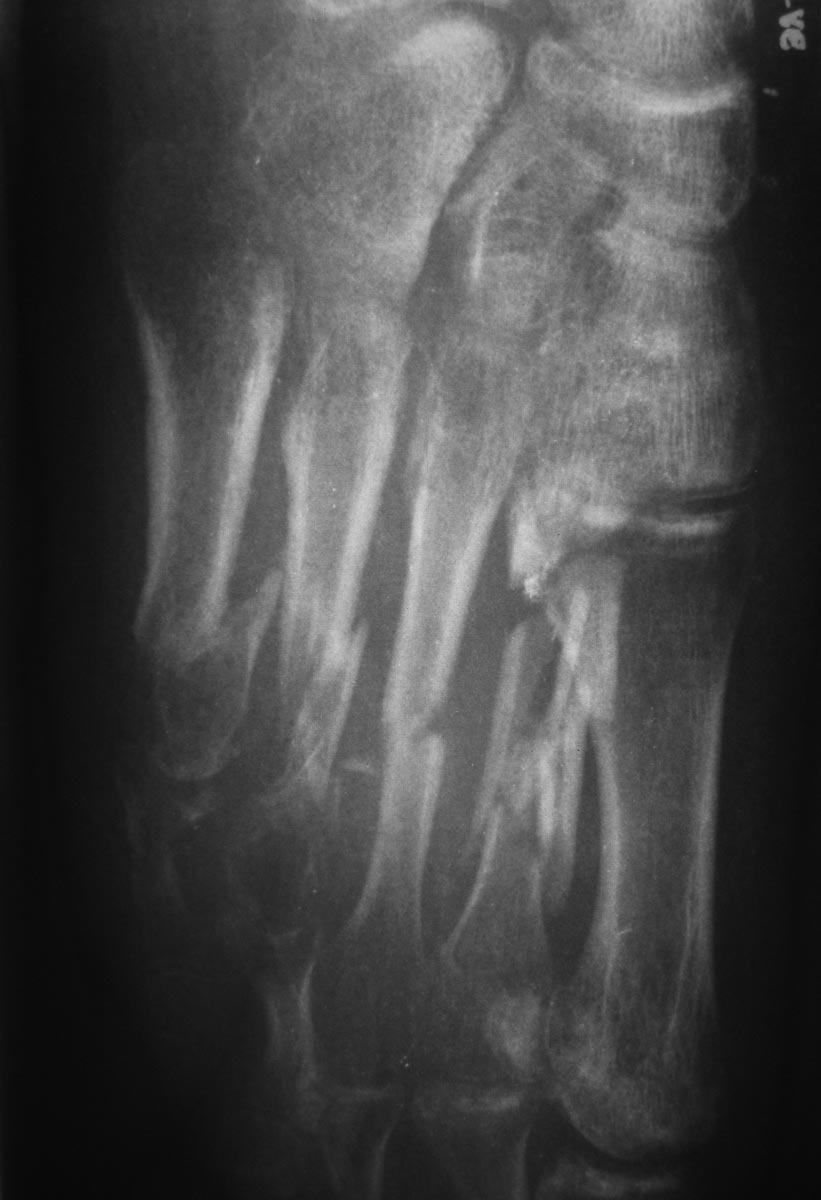

Пациентка 19 лет 11.05.13 получила травму в результате ДТП. диагноз: Открытые 3а степени оскольчатые переломы диафиза 2-5 плюсневых костей, перелом проксимальной фаланги 5 пальца, разрыв сухожилия разгибателя 4 пальца правой стопы.

При поступлении выполнено ПХО открытых переломов, фиксация спицами. Рана тыла стопы заживала без воспаления, однако имелся частичный некроз кожного лоскута. По снятии швов произведена иммобилизация циркулярной повязкой. Снимки стопы через 2,5 мес. иммобилизации.

Кроме переломов плюсневых костей, как мне кажется, есть подвывих в суставе Лисфранка (2-3 плюсне-клиновидный) суставы.

Проксимальная головка II плюсневой в вывихе (?), IV-V плюсневые выполнил бы МОС с резекцией костной мозоли. Можно ЧЛХ мини пластинами типа "Конмет". Одновременно шов разгибателя или его пластика поверхностным разгибателем с другого пальца. Случай не простой. Желаю удачи.

Мне кажется, что продолжение иммобилизации через такой срок смысла не имеет. Она и так уже привела к развитию резко выраженного остеопороза. Нужно снимать гипс, давать нагрузку на стопу до легко терпимых болезненных ощущений в обуви на жесткой подошве. Если пациентка сможет ходить с полной нагрузкой - пусть ходит. Нагрузка в подобной ситуации должна ускорить сращение и постепенно уменьшить выраженность регионарного остеопороза. И со временем, по мере сращения костей и восстановления опороспособности стопы нужно будет уже решать, нужна ли операция и если нужна, то какая (укорочение ли сохранивших длину 1 и 3 плюсневых, артродез поврежденных суставов среднего отдела стопы или еще что).

Для формирования продольного свода стопы достаточно сильное смещение отломков 5-й плюсневой кости - возможно именно на это стоит обратить внимание. Все остальное должно срастись без проблем